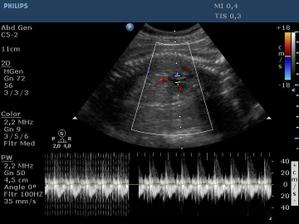

Ultrazvuk miminka - 24 týden

Z "menší protekce" u pana primáře Radiodiagnostického oddělení jsme mohli na soukromou "špionáž" naší krásné holčičky... (Pan doktor je už třetí, kdo hádá holčičku a po pravdě s tím přístrojem, co má k dispozici, bylo naprosto zřetelně vidět, že tam žádný pytlík není! :o)) Natočil nám i několik videí, kde ta naše šibalka zívala a dvakrát na nás dokonce vyplazovala jazyk. ;o)